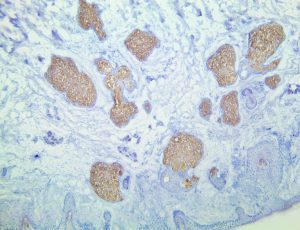

Bio SB has developed high affinity IVD monoclonal antibodies for fast immunohistochemistry (IHC) detection of melanoma, basal cell carcinoma (BCC), squamous cell carcinoma (SCC) and other Mohs surgery related conditions. Combined with our innovative IHC detection systems, we are opening the doors to a faster and more accurate immunohistochemistry applicable to Mohs surgery.

Bio SB has developed a fast, non-biotin monovalent Fab micropolymer IHC detection system for the detection of IVD antibodies for melanoma, BCC, SCC and other Mohs surgery related conditions. Our innovative IHC detection systems have opened the doors for a faster and accurate immunohistochemistry applicable to Mohs surgery.